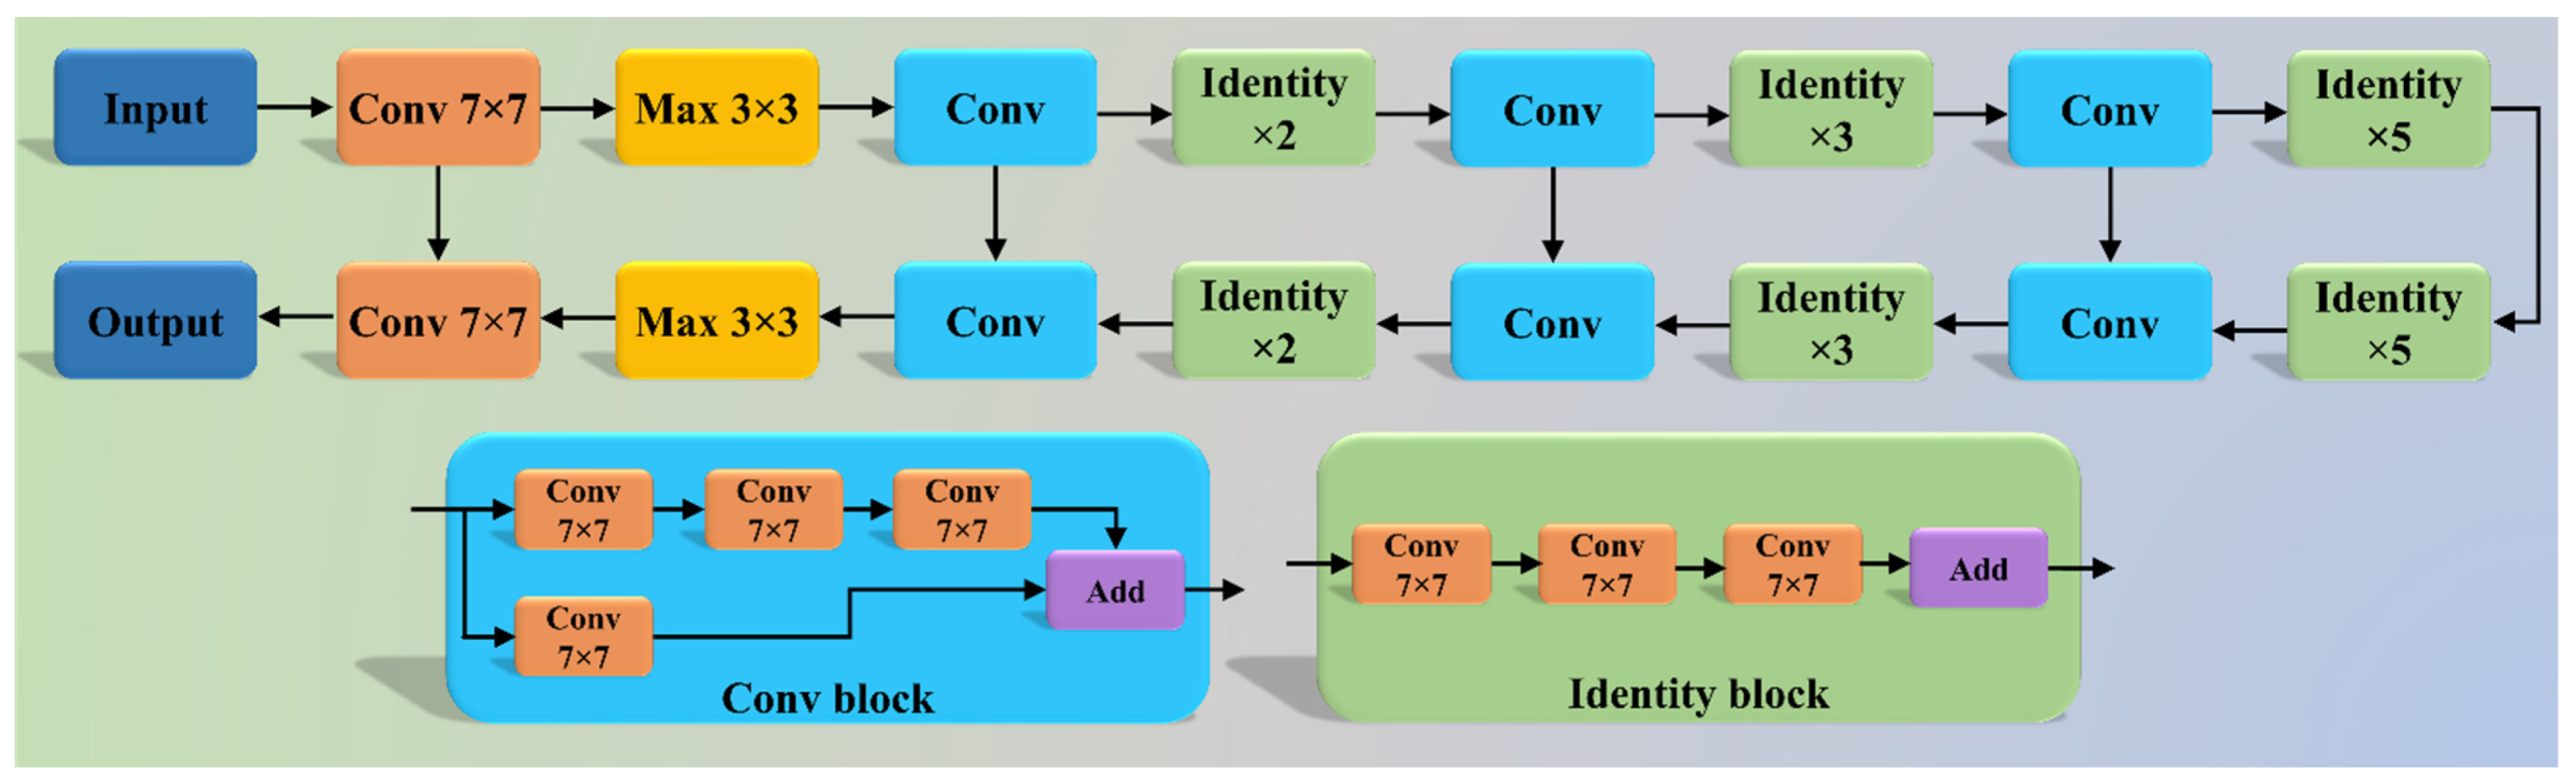

2.2. Architecture

2.2.1. Three AI Models: PSP Net, VGG-SegNet, and ResNet-SegNet